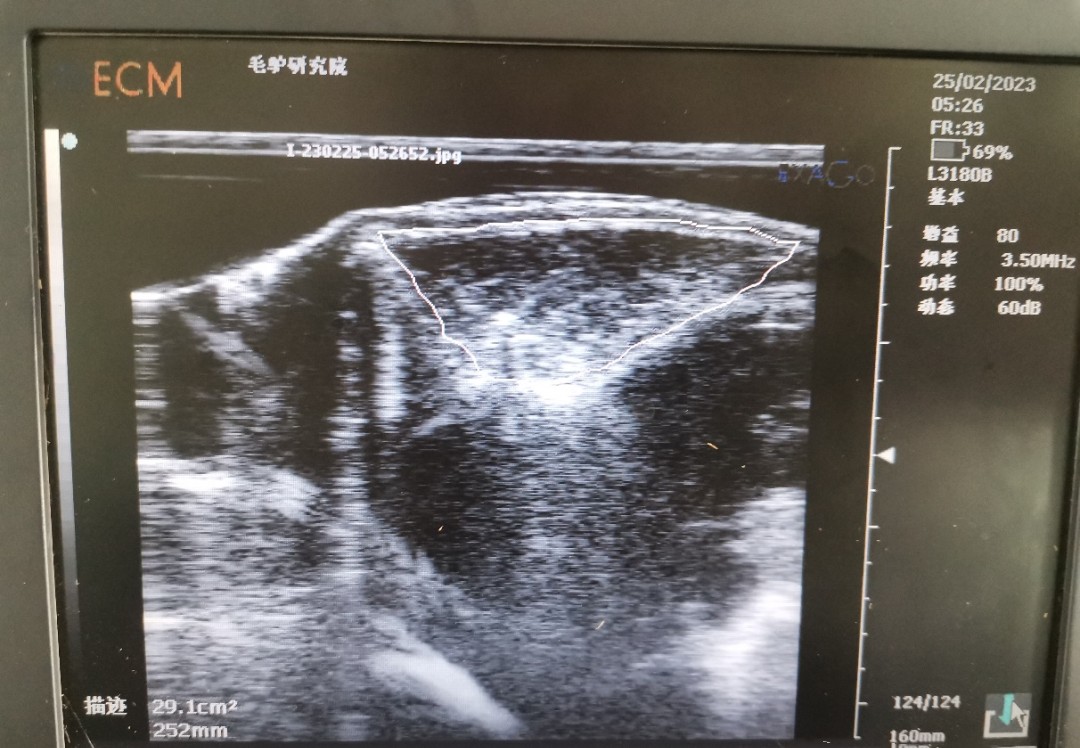

背膘活體測定可反應(yīng)家畜的膘情,而家畜的膘情與繁殖性狀相關(guān)。已有研究表明,豬的背膘和眼肌面積的研究已經(jīng)非常成熟,豬的背膘厚與繁殖性狀相關(guān),眼肌面積與生產(chǎn)性狀相關(guān)。同時(shí),近年來在牛上也陸續(xù)開展背膘和眼肌面積工作的測定。背膘厚度及眼肌面積的活體測定,在指導(dǎo)動(dòng)物的生產(chǎn)、精準(zhǔn)飼喂、動(dòng)物的遺傳改良中發(fā)揮較好作用,使家畜育種和生產(chǎn)工作取得了較大進(jìn)展。但此技術(shù)在驢上應(yīng)用卻較少。

為了彌補(bǔ)背膘和眼肌面積在驢上的應(yīng)用空白,我團(tuán)隊(duì)開展了德州驢背膘和眼肌面積的測定工作。為更好的驗(yàn)證所測定的結(jié)果,團(tuán)隊(duì)成員在已屠宰的德州驢上進(jìn)行確認(rèn),確保測量結(jié)果準(zhǔn)確性。背膘厚及眼肌面積性狀在驢遺傳育種上的應(yīng)用將為選育更加優(yōu)良的德州驢種質(zhì)提供了新的指標(biāo),可加快驢種質(zhì)創(chuàng)新步伐。